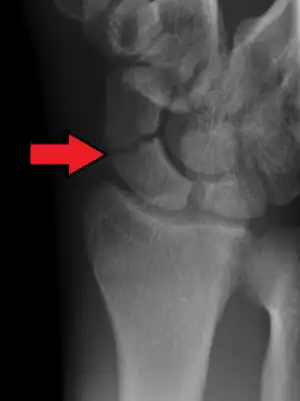

A more obvious scaphoid fracture on a scaphoid view X ray